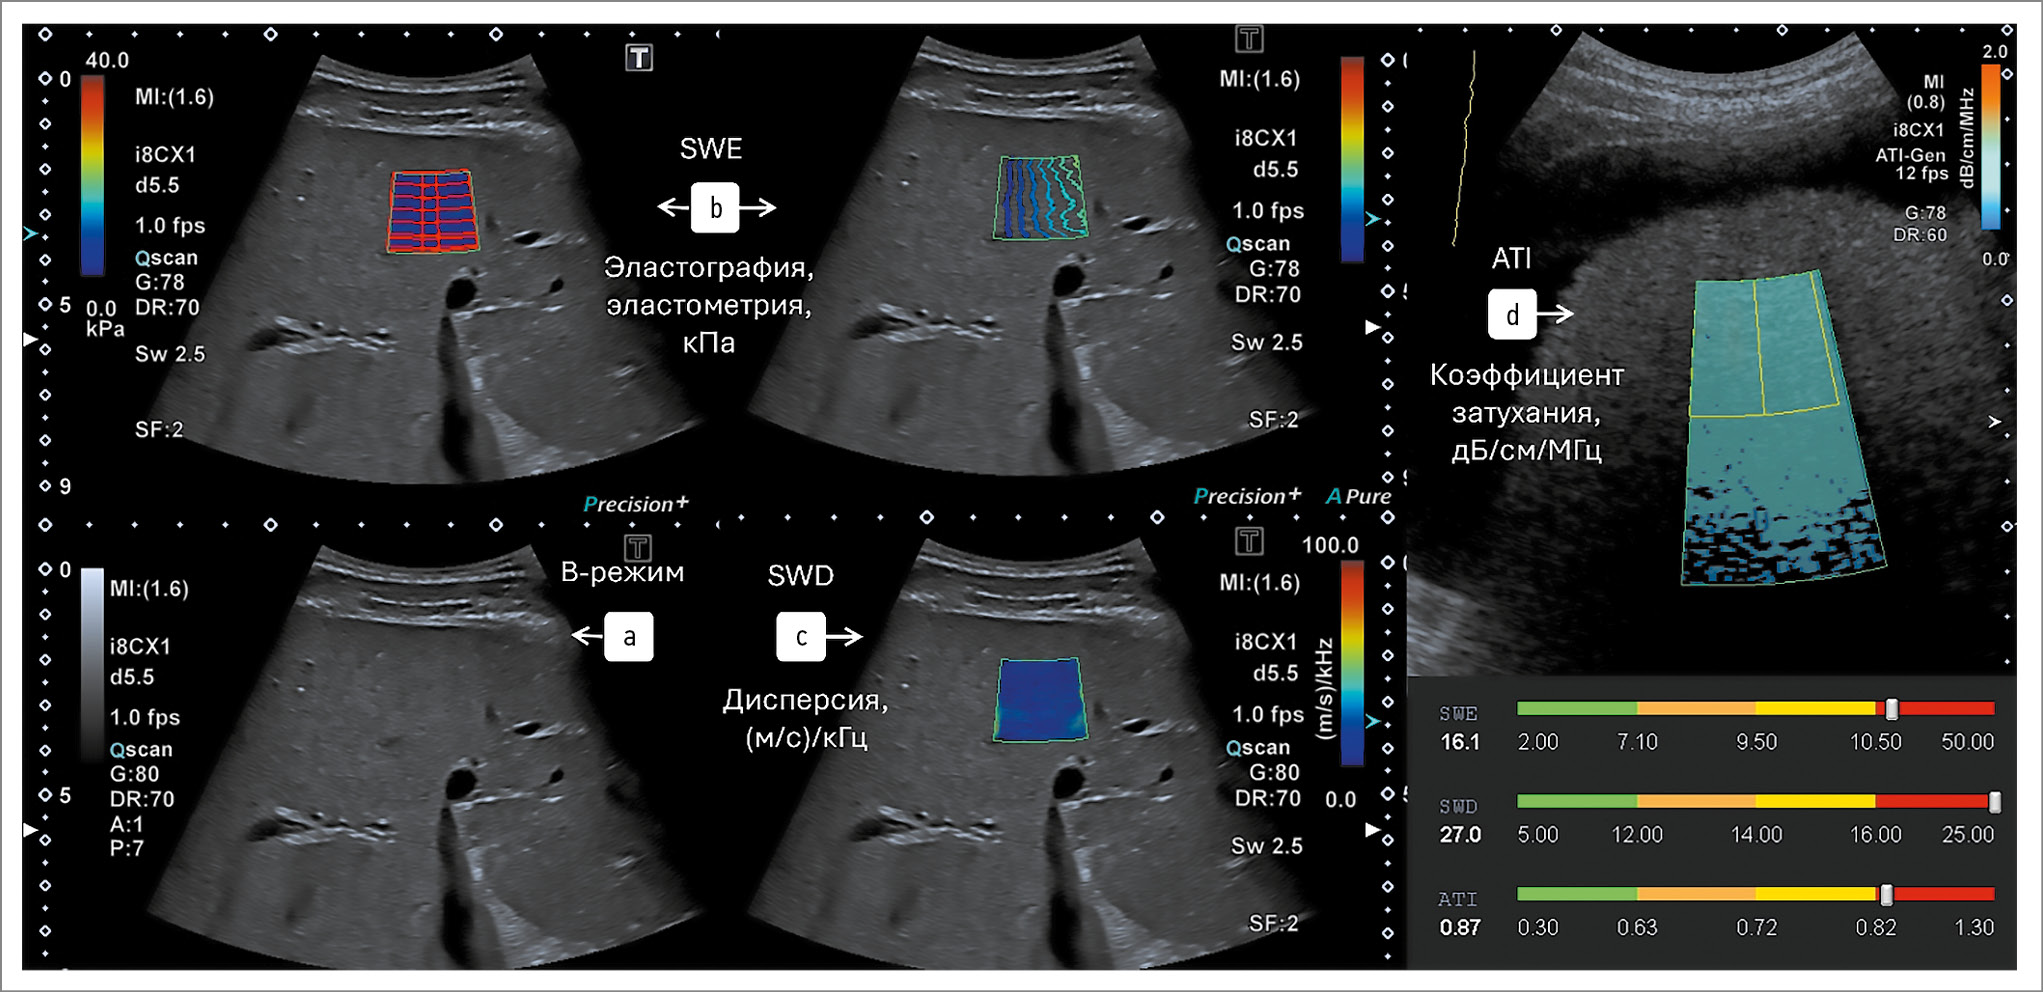

Рис. 4. Оптимальный ультразвуковой комплекс мультипараметрического исследования для пациентов со СБП с количественной оценкой диффузных изменений печени:

а – оценка в В-режиме; b – эластография, эластометрия – оценка жесткости; c – режим дисперсии – оценка воспалительной активности; d – оценка АС ультразвуковой волны – оценка стеатоза печени.

По данным двумерной ультразвуковой эластографии сдвиговой волной у 41 (8,1%) пациента выявлен фиброз печени F1-F2, у 29 (5,75%) пациентов – фиброз печени F3, у 11 (2,2%) пациентов – цирроз печени.

Предлагаемый вариант оптимального комплекса мультипараметрического исследования для пациентов со СБП с количественной оценкой стеатоза, воспаления и фиброза представлен на рис. 4 (не зависит от коммерческого названия и фирмы-производителя в случае наличия возможности комплексной оценки всех клинико-морфологических форм СБП).